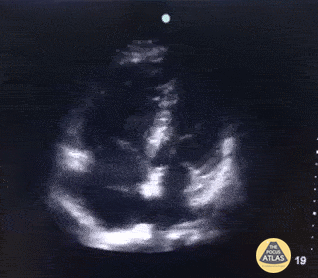

Right Ventricular Dysfunction - Right Atrial Thrombus

A 70 year old female patient with complaints of acute dyspnea. Oxygen saturation 86% with room-air improved with O2-suppletion. Poor hemodynamics with systolic presure around 100 mmHg. POCUS shows obvious right heart strain with apical sparing (McConnel's sign) and trombus drifting around in right atrium and even hitting the right ventricle. Correct therapy (trombolytics) was started almost straight away after presentation at the ED because POCUS was available. Dr. Van Roosmalen